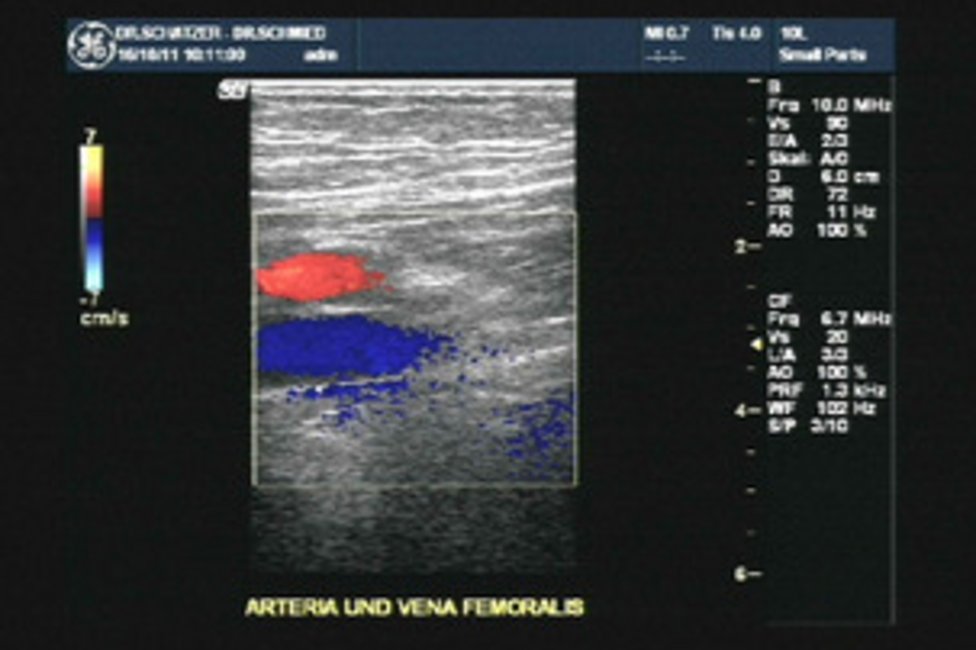

Folgende Diagnoseverfahren werden routinemäßig durchgeführt: Farbkodierte Duplexsonographie (inkl. Kompressionssonographie bei Thromboseverdacht), Plethysmographie und arterielle Ausmessung (Oszillometrie).